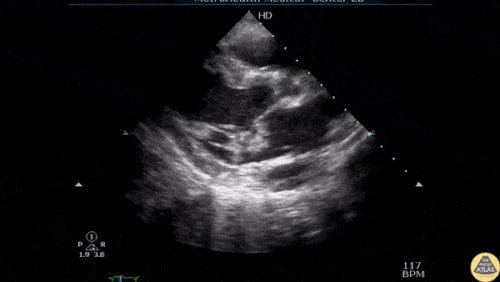

01 - LV dysfunction in PLAX